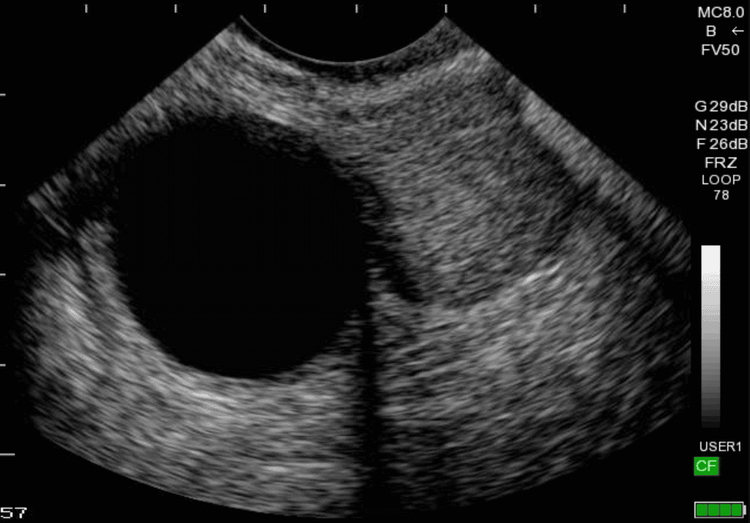

•    Ovarian cysts: A common condition in women that often presents without noticeable symptoms. Routine gynecological ultrasound screenings are essential for early detection.

Ultrasound image of an ovarian cyst